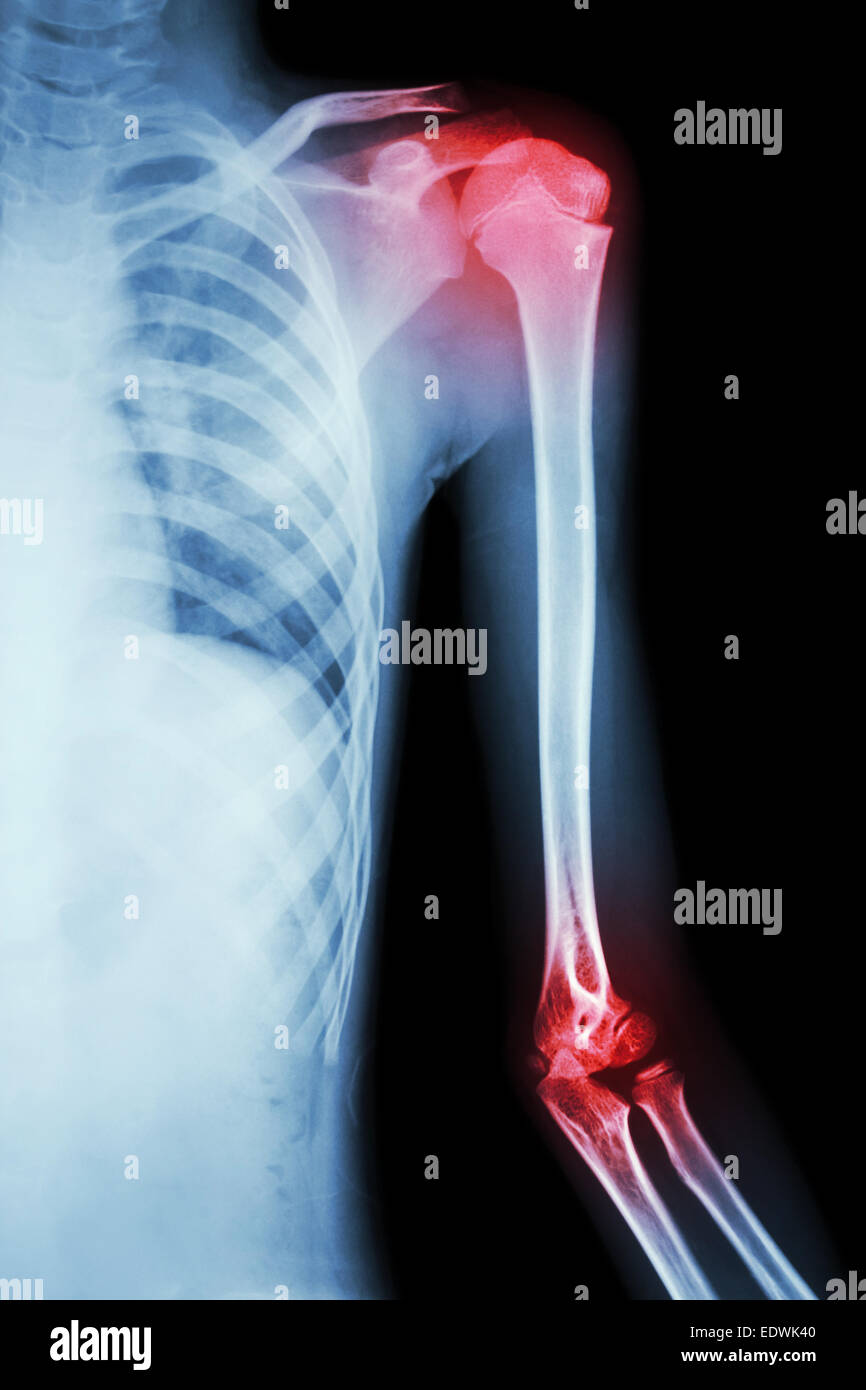

Left Elbow X-Ray Film . In adults, elbow dislocation is the second most common. Web the elbow series is a set of radiographs taken to investigate elbow joint pathology, often in the context of trauma.

Fractures lines can be difficult to visualize after acute elbow injury, particularly in children. The osseous anatomy of the elbow is complex, and fractures can occasionally be radiographically occult or. Web this view is clinically indicated for trauma to, chronic discomfort or infection of the elbow joint.

Web this view is clinically indicated for trauma to, chronic discomfort or infection of the elbow joint. It aids in visualizing fractures and/or. Web elbow fractures and dislocations are commonly seen in the acute care setting. Fractures lines can be difficult to visualize after acute elbow injury, particularly in children.

Left Elbow X-Ray Film - In adults, elbow dislocation is the second most common. The osseous anatomy of the elbow is complex, and fractures can occasionally be radiographically occult or. Web the elbow series is a set of radiographs taken to investigate elbow joint pathology, often in the context of trauma. Your elbow bones include the upper bone of your elbow joint (humerus) and the..